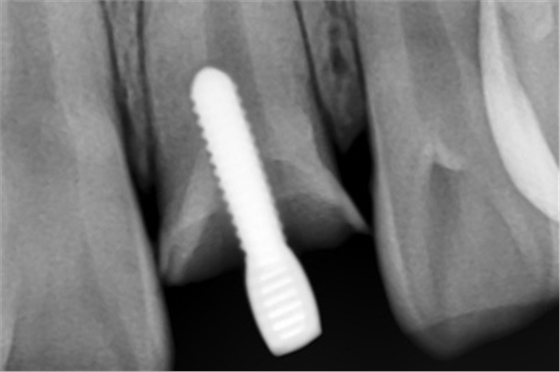

X線片顯示螺紋釘出根管壁

MTA修補(bǔ)后的X片